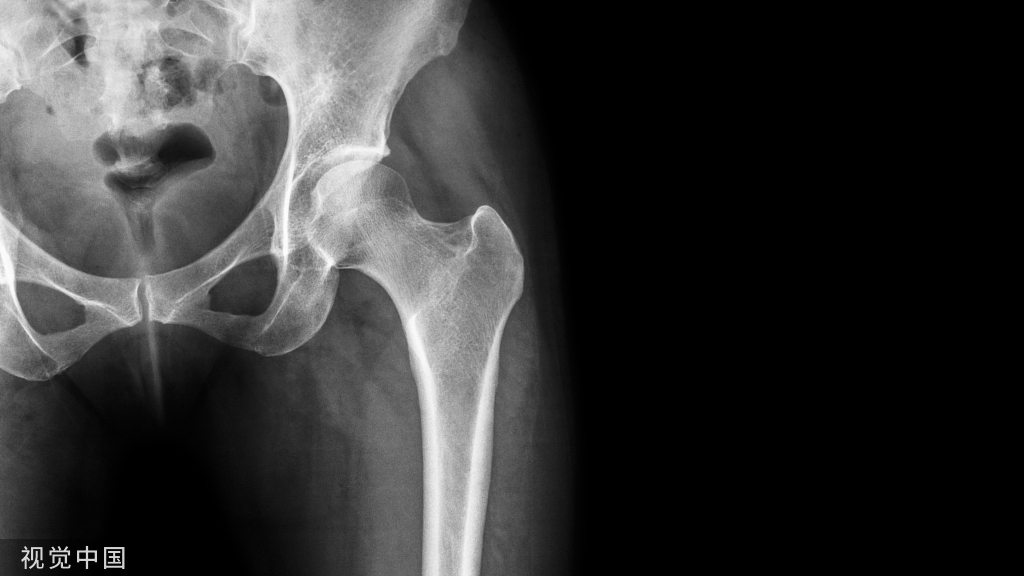

几十年来,稳定的中性下肢力线是全膝关节置换术(TKA)的首要原则,因为其可获得长期的临床疗效和假体生存率。

然而,这种机械对线技术【Mechanical Alignment (MA) technique】TKA,不是为了恢复患者固有的个体化力线,而是系统性的创建一个“生物力学友好型人工膝关节”因此,有学者认为尽管MA-TKA提供了满意的长期假体生存率,但是术后患者满意度不尽人意(80%左右)(个人对这一满意度有所保留,从我目前随访的患者来看,患者术后1年满意度可达95%左右)